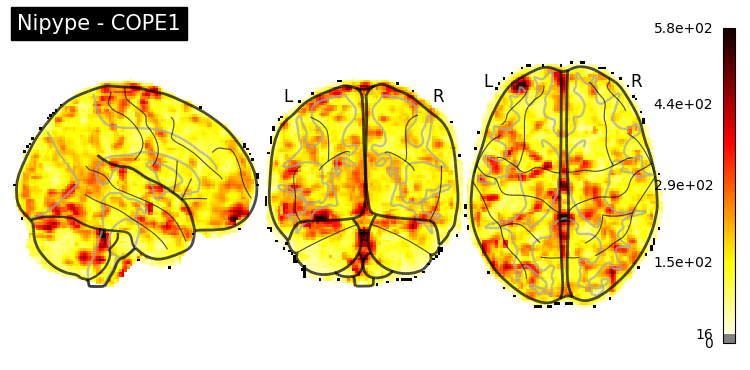

The first-level GLM#

Here we randomly choose the four copes from subject-09 run-1

nipype_cope1 = './output_level1/level1_results/09/results_dir/_subject_id_09/_level1estimate0/results/cope1.nii.gz'

nipype_cope2 = './output_level1/level1_results/09/results_dir/_subject_id_09/_level1estimate0/results/cope2.nii.gz'

nipype_cope3 = './output_level1/level1_results/09/results_dir/_subject_id_09/_level1estimate0/results/cope3.nii.gz'

nipype_cope4 = './output_level1/level1_results/09/results_dir/_subject_id_09/_level1estimate0/results/cope4.nii.gz'

plotting.plot_stat_map(nipype_cope1, bg_img=nipype_cope1, title = 'Nipype - COPE1', cmap = 'bwr', colorbar = False)

plt.show()

plotting.plot_stat_map(nipype_cope2, bg_img=nipype_cope1, title = 'Nipype - COPE2', cmap = 'bwr', colorbar = False)

plotting.plot_stat_map(nipype_cope3, bg_img=nipype_cope1, title = 'Nipype - COPE3', cmap = 'bwr', colorbar = False)

plotting.plot_stat_map(nipype_cope4, bg_img=nipype_cope1, title = 'Nipype - COPE4', cmap = 'bwr', colorbar = False)

../../_images/a7f7f387884673a96e62aa7d2d938a6b6487846759bc4500b6d0cff677c7358d.png ../../_images/bc743ce13891ebab23c9f6c7d4d668db8d11c9409d4f6e4580f7d63b35ecdb77.png ../../_images/228b3b22c00177a8ad5dc1793cbbc90dbfb495735196a4af47e73b899de0ca82.png ../../_images/babe8f68f0856f0f1608dfe550483d8ca862aae33a659d1f970a9fbe726f3bb1.png